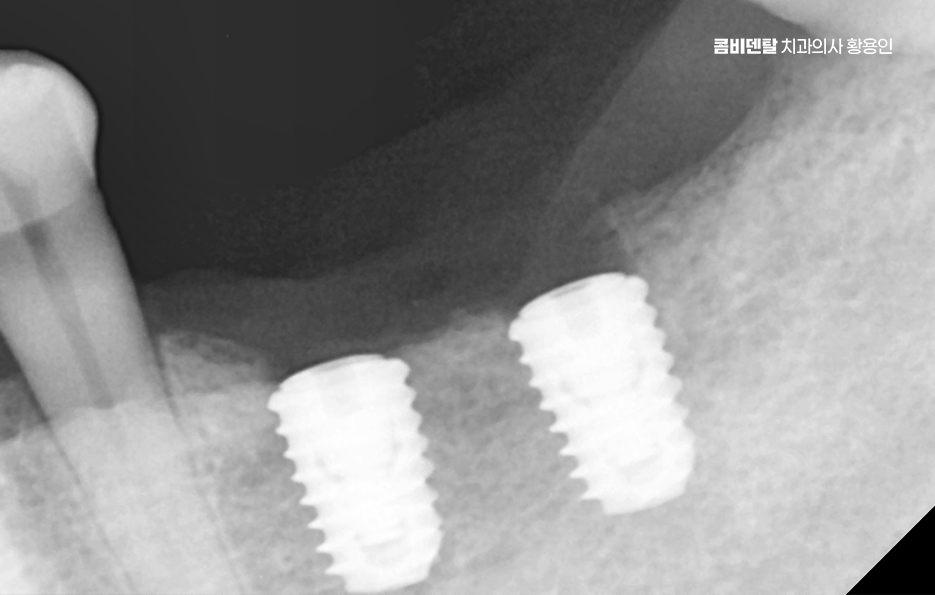

그렇다면 어금니 발치 후, 임플란트를 잘 받기 위한 방법은 뭐냐 하면 첫 번째는 시기를 놓치지 않는 것인데 발치 후 3개월 내에는 임플란트를 심는 게 이상적이며 사실 요즘은 경우에 따라 ‘즉시 식립’이라고 해서 발치 당일에 임플란트를 심는 경우도 많아지고 있기 때문에 발치와 함께 임플란트 치료 계획을 세우는 것이 이상적이라 할 수 있어요

나에게 맞는 치료를 하기 위해서는 정확한 진단과 설계가 중요하며 CT 촬영 등을 통해 신경 위치, 뼈의 양, 두께 등을 정밀하게 진단한 다음, 교합과 치열 구조에 맞는 위치에 임플란트를 심는 게 중요한데 잘못된 위치에 심어지면 오래 쓰기 어렵고, 나중에 통증이나 염증이 생길 수 있었어요.

임플란트는 처음 수술보다 이후 관리가 더 중요하다고 할 정도니까, 처음부터 잘 설계된 치료계획 아래 수술을 받는 게 중요하며 그 이후로도 사후관리를 잘하는 것이 곧 임플란트의 수명 유지에 중요한 거예요